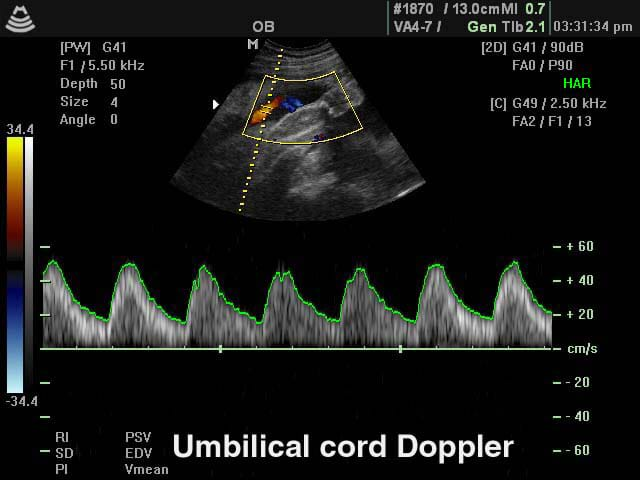

Your frequency of visits will increase; every 2 weeks until 36 weeks and weekly thereafter. This is because most pregnancy complications, such as high blood pressure, occur in the later stages of pregnancy. Your obstetrician will perform an ultrasound at 28 weeks to ensure that your baby is growing well. You will have blood tests repeated to check for anaemia. A low vaginal swab is usually collected at 36 weeks gestation to screen for Group B Streptococcus. The 3rd Trimester care focuses on the health of the baby, in order to have it in the best possible condition before birth. We have various ways of assessing the baby's wellbeing including CTG, ultrasound for growth and fetal welfare studies. Finally, your birth plan and delivery options will be discussed at length to cater for you individual choices. |